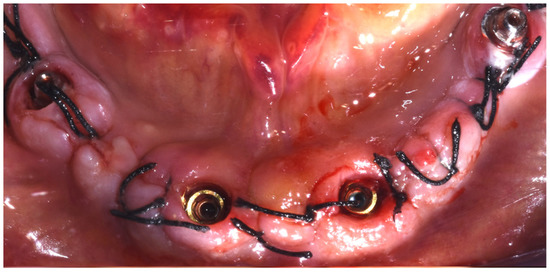

Surgery Appointment